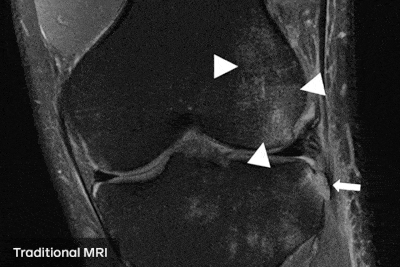

A través del estudio del equipo de investigación de inteligencia artificial de Facebook (FAIR) junto a radiólogos de NYU Langone Health se descubrió que es posible hacer resonancias magnéticas cuatro veces más rápido si se utiliza inteligencia artificial. Lo más importante es que las imágenes obtenidas conservan la calidad de las resonancias tradicionales.

El trabajo lleva el nombre de fastMRI y para llevarlo a cabo se entrenó a una máquina con muestras de resonancias de baja y alta resolución, utilizando esto para predecir cómo debería verse el resultado de una resonancia con solo un cuarto de la información que normalmente se procesa. Teniendo en cuenta que los resultados generales fueron buenos, esto puede representar un alivio tanto para pacientes como para médicos, ya que implica tener diagnósticos en menor tiempo.